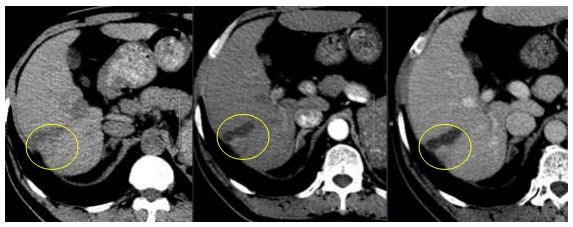

– Đánh giá về hình ảnh:

Hình 6: Hình ảnh CT bụng sau 9 tháng: Vùng giảm tỷ trọng hạ phân thùy VI, kích thước 2,6×3,2 cm, không ngấm thuốc (vòng tròn vàng)

Hình 7: Hình ảnh CT bụng tháng sau 12 tháng: Vùng giảm tỷ trọng hạ phân thùy VI, KT 3,1×1,0cm, không ngấm thuốc, co kéo bờ gan (vòng tròn xanh nhạt)

Hình 8: Hình ảnh CT ổ bụng sau 24 tháng: Vùng giảm tỷ trọng hạ phân thùy VI, KT 3,0×1,0cm, không ngấm thuốc, gây co kéo bờ gan (vòng tròn tím)

Hình 9: Hình ảnh CT ổ bụng sau 36 tháng: Vùng giảm tỷ trọng hạ phân thùy VI, KT 2,9×1,0cm, sau tiêm không ngấm thuốc, co kéo bờ gan (vòng tròn xanh đậm)

Nhận xét: Trước điều trị khối u ngấm thuốc điển hình của HCC (hình 5), tuy nhiên sau điều trị ở thời điểm 9 tháng trở đi khối u giảm về kích thước, không ngấm thuốc sau tiêm nên đạt được bệnh đáp ứng hoàn toàn theo tiêu chuẩn mRECIST (hình 6,7,8,9).